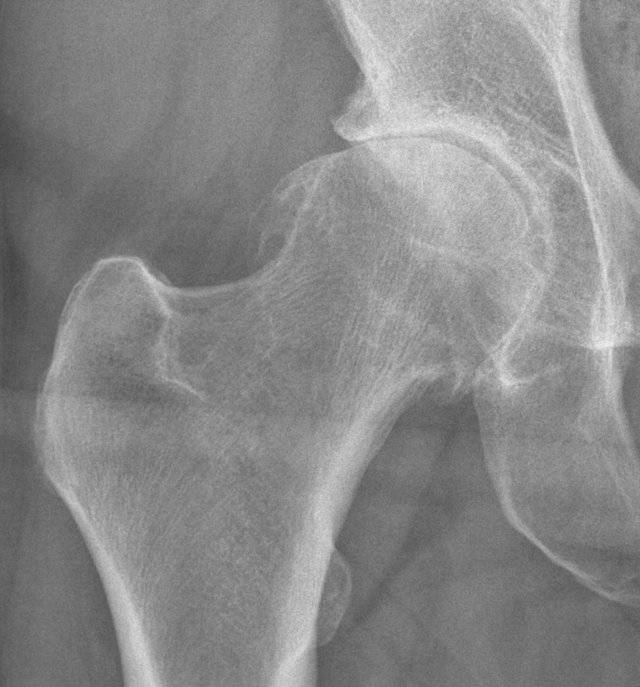

Coxarthrose (deutsch: Koxarthrose oder Hüftarthrose) ist eine degenerative, nicht-entzündliche Gelenkerkrankung der Hüfte: Die Knorpelschicht zwischen Hüftkopf und Hüftpfanne nutzt sich langsam fortschreitend ab. Wenn der Gelenkknorpel schließlich dünner wird, drohen die knöchernen Gelenkflächen aufeinanderzureiben.. Den Verschleiß des Hüftgelenkes bezeichnet der Mediziner als Coxarthrose. Diese kann sowohl unter Belastung, aber auch im Ruhezustand zu starken Schmerzen führen. Ferner kann die Beweglichkeit des Gelenks deutlich eingeschränkt sein. Woran erkennt man eine mögliche Hüftgelenksarthrose? Wann ist eine Operation sinnvoll?